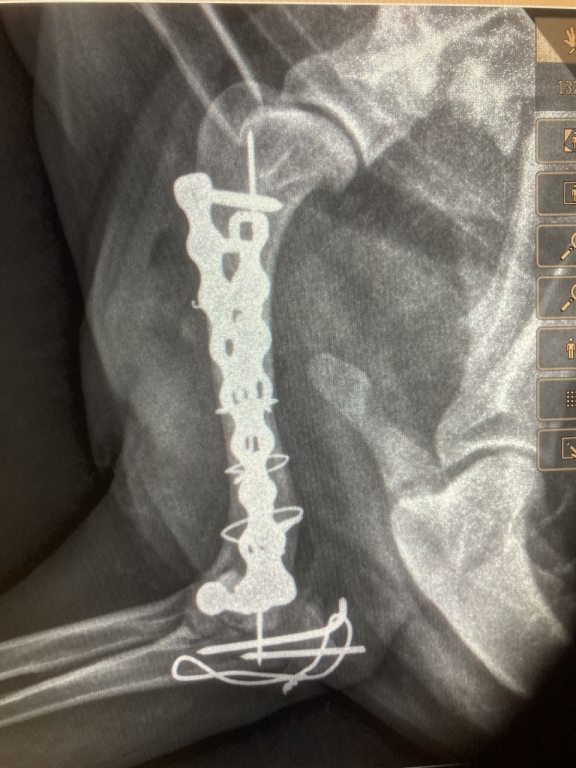

A leading veterinary surgeon who successfully operated on a Cocker Spaniel’s gruesomely fractured leg, has described the injury as ‘memorably horrible’.